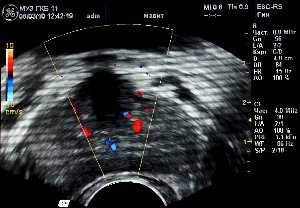

Для оценки биотканевого влияния устройства «МАВИТ» на кровообращение ПЖ и окружающие ткани у 10 больных из второй группы (ХП) до и после физиотерапевтического сеанса проводилось трансректальное ультразвуковое исследование ПЖ в режиме цветного доплеровского картирования. Изучалась линейная пиковая скорость кровотока, индекс периферического сосудистого сопротивления, а также плотность органного сосудистого рисунка.

Для оценки состояния кровотока в предстательной железе после сеанса локальной физиотерапии на устройстве «МАВИТ» у 10 больных второй группы (ХП) проведено трансректальное ультразвуковое исследование ПЖ в режиме цветного доплеровского картирования до и после лечебного сеанса, показавшее улучшение микроциркуляции в ткани предстательной железы. Применение аппарата «МАВИТ» приводит к выраженной реакции в виде усиления кровообращения по всему сосудистому коллектору (см. рис. 1 и 2). Средний показатель линейных пиковых скоростей в изученной подгруппе увеличился в 1,1 раза, уменьшилась величина индекса резистентности в 1,2 раза в сравнении с исходными данными. Средний показатель плотности сосудистого рисунка увеличился более чем в 2,5 раза.

Рис.1 Рис.2

Рисунок 1: Б-ой П., 38 лет. Доплерограмма перед сеансом физиотерапии на устройстве «МАВИТ».

Рисунок 2: Доплерограмма того же больного после сеанса физиотерапии на устройстве «МАВИТ».